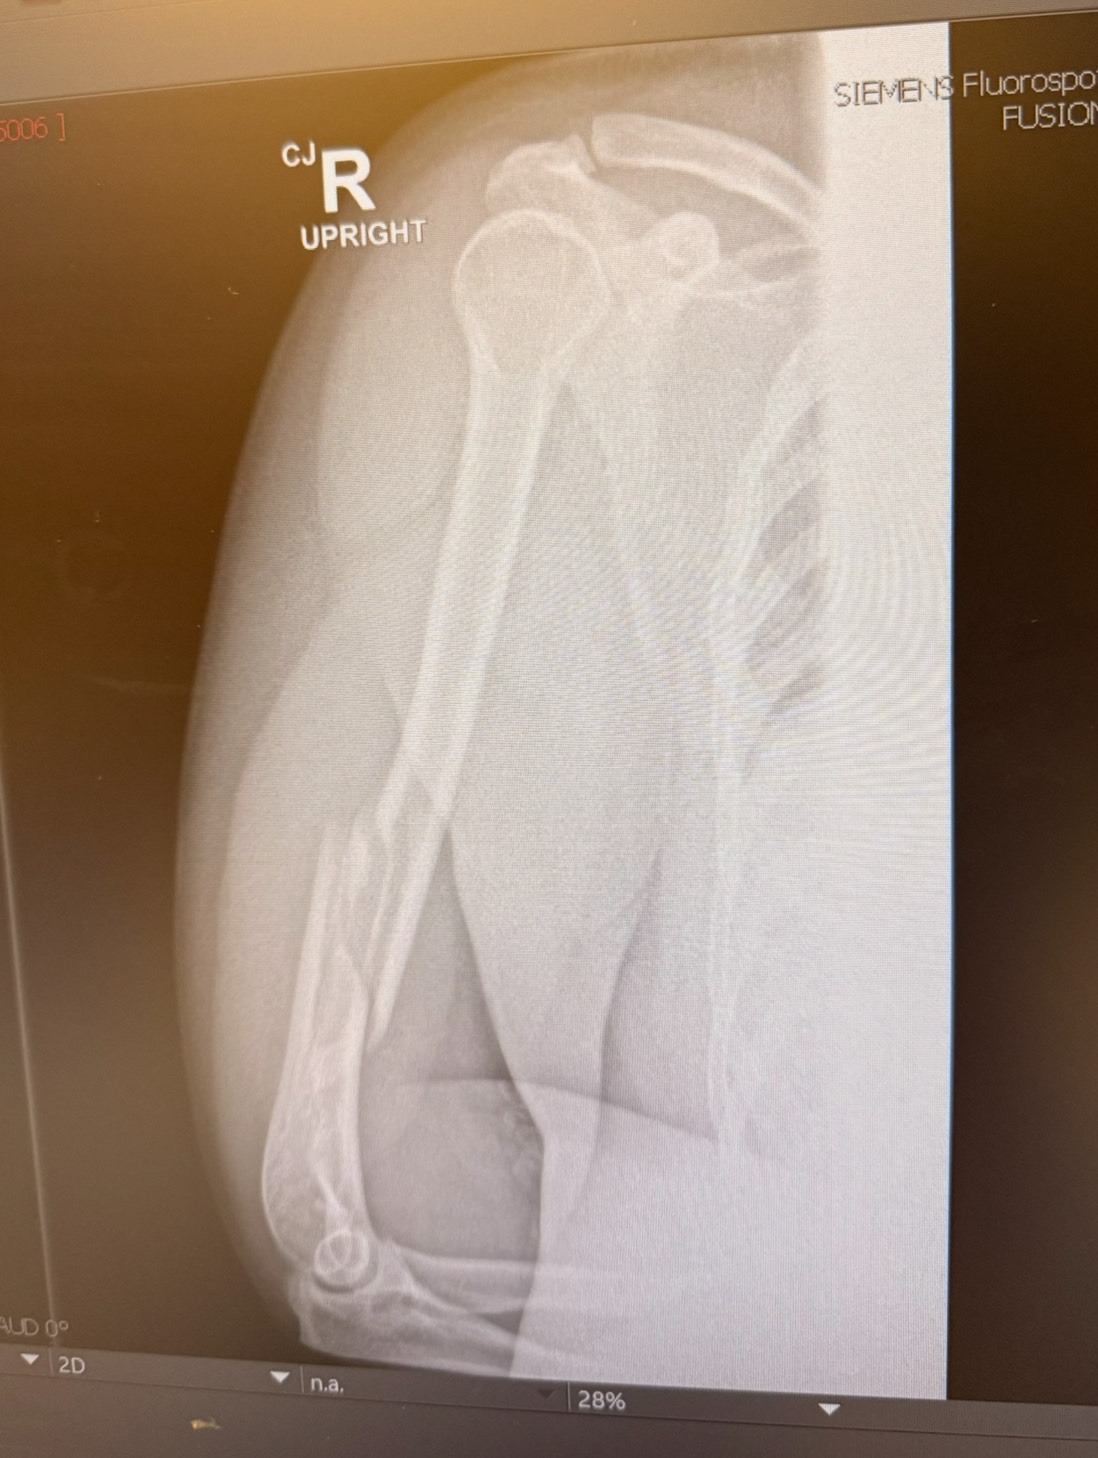

After competing at a local queer arm wrestling event my humerus was unfortunately broken and has put me out of commission foreseeable future. While I am fortunate enough to have insurance and most of the medical expenses are taken care of, I am still going to need some additional funds to help transition through the next few months while I am on my healing journey.

I am a med student and have a fixed income because of lack of ability to work while I am finishing up my degree and right now am gearing up to take my Level 1s so stress levels are high and this injury is most certainly adding to them in a major way.